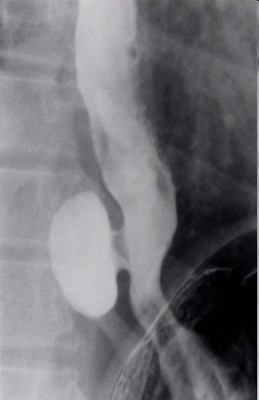

- Kontrastlı Rh-qrafiya - diaqnozu dəqiqləşdirən müayinədir.

- Rentgenoqrafik divertikul görünməsi

- Kontrastlı Rh-qrafiya - dəqiqləşdirici müayinə üsuludur.

- Kontrastlı müayinələrdə (Rh-qrafiya, KT) divertikul görünməsi

Kontrast məhlulunn divertikul nahiyəsində toplanması

Kontrast məhlulun divertikul nahiyəsində toplanması